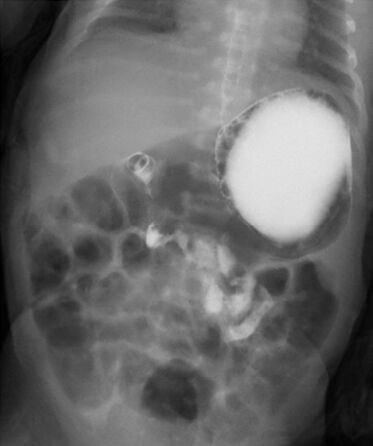

74.出生兩天大的女嬰因嘔吐不止就醫,接受上消化道攝影結果如圖示,下列何者為最可能之診斷? (A)中腸旋轉不良 (B)肥厚性幽門狹窄 (C)胃食道逆流 (D)空腸閉鎖症